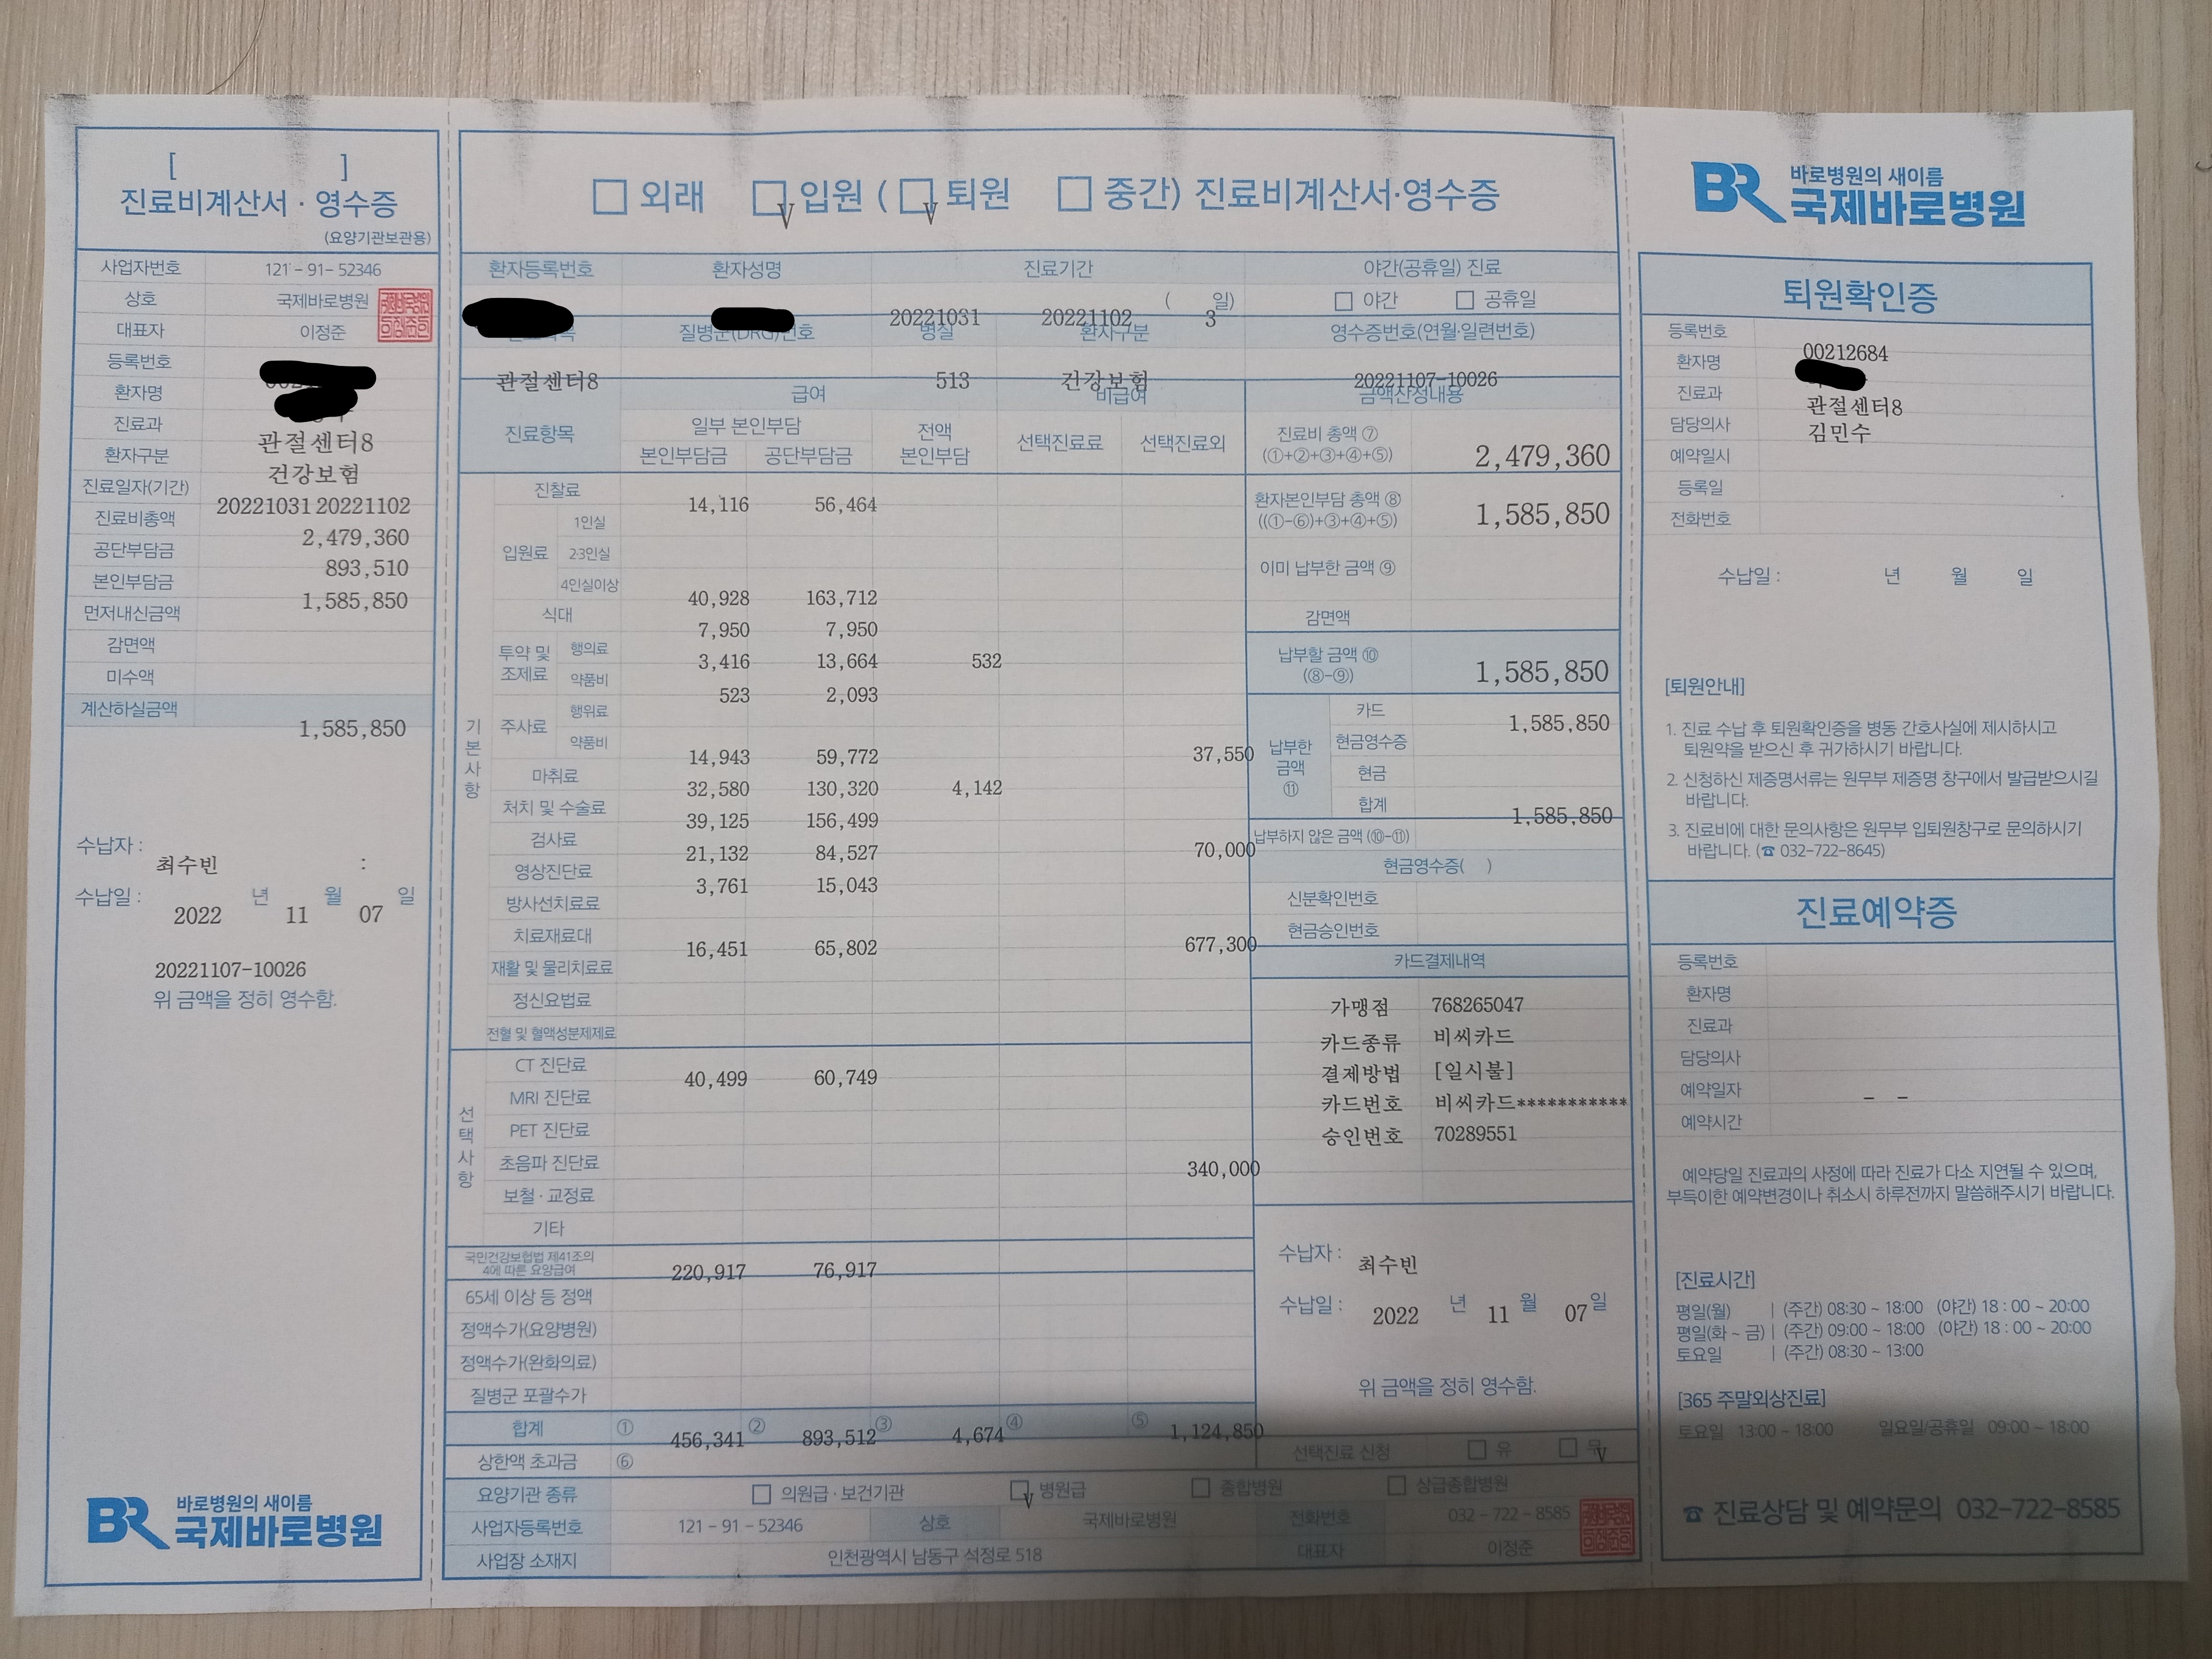

진료비

진료비는 총합 1,585,850 원이 나왔습니다.

저는 따로 실비 들어 논게 있었는데 실비에서는 120만원정도 나왔습니다.